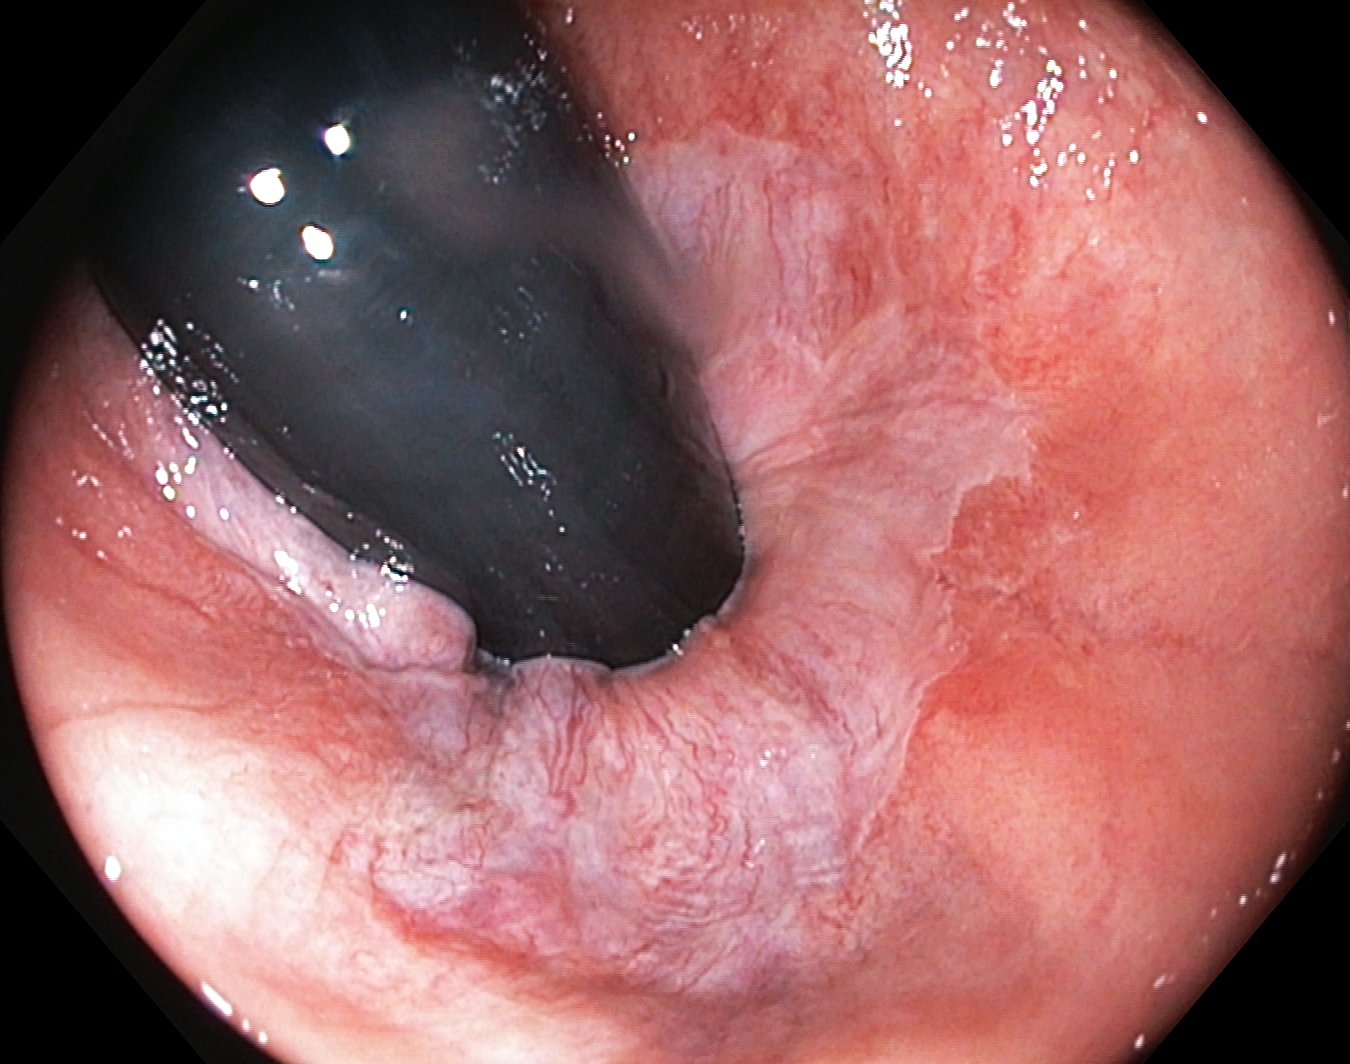

Linea dentata/anorectalis seen with the endoscope in an inverted position